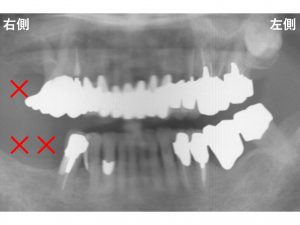

先日手術が終わったばかりのケースです。

患者様は、奥歯で噛めなくなってきて、

食事が十分取れないとのことでした。

以下が治療前です。

下顎右側の奥歯が欠損しています。

そのため、右側の奥歯で噛めない状態です。

上顎にも問題があります。

上顎左側奥歯の歯肉が腫れています。

またグラグラして噛めない状態です。

上顎左側の奥歯の2歯は、

歯の根が折れている状態です。

歯根破折です。

また歯周病も進行していました。